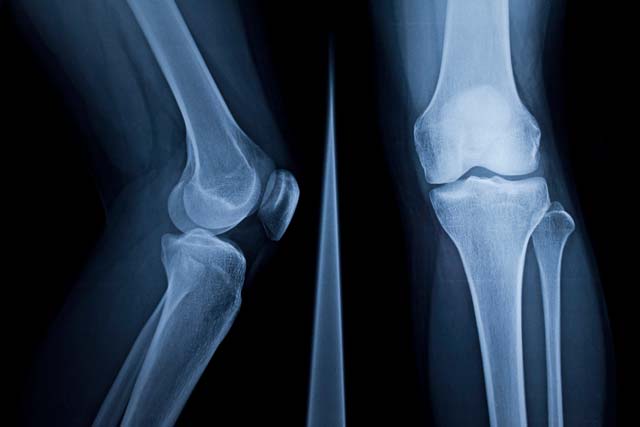

“Limb Reconstruction” refers to the subspecialty of orthopaedic surgery that deals with problems in which a limb is the wrong shape or length, and function is affected.

Limb Reconstruction refers to a field of Orthopaedics that uses biological treatment for patients with limb length inequality, deformity and deficiency in order to restore and preserve function in both children and adults.